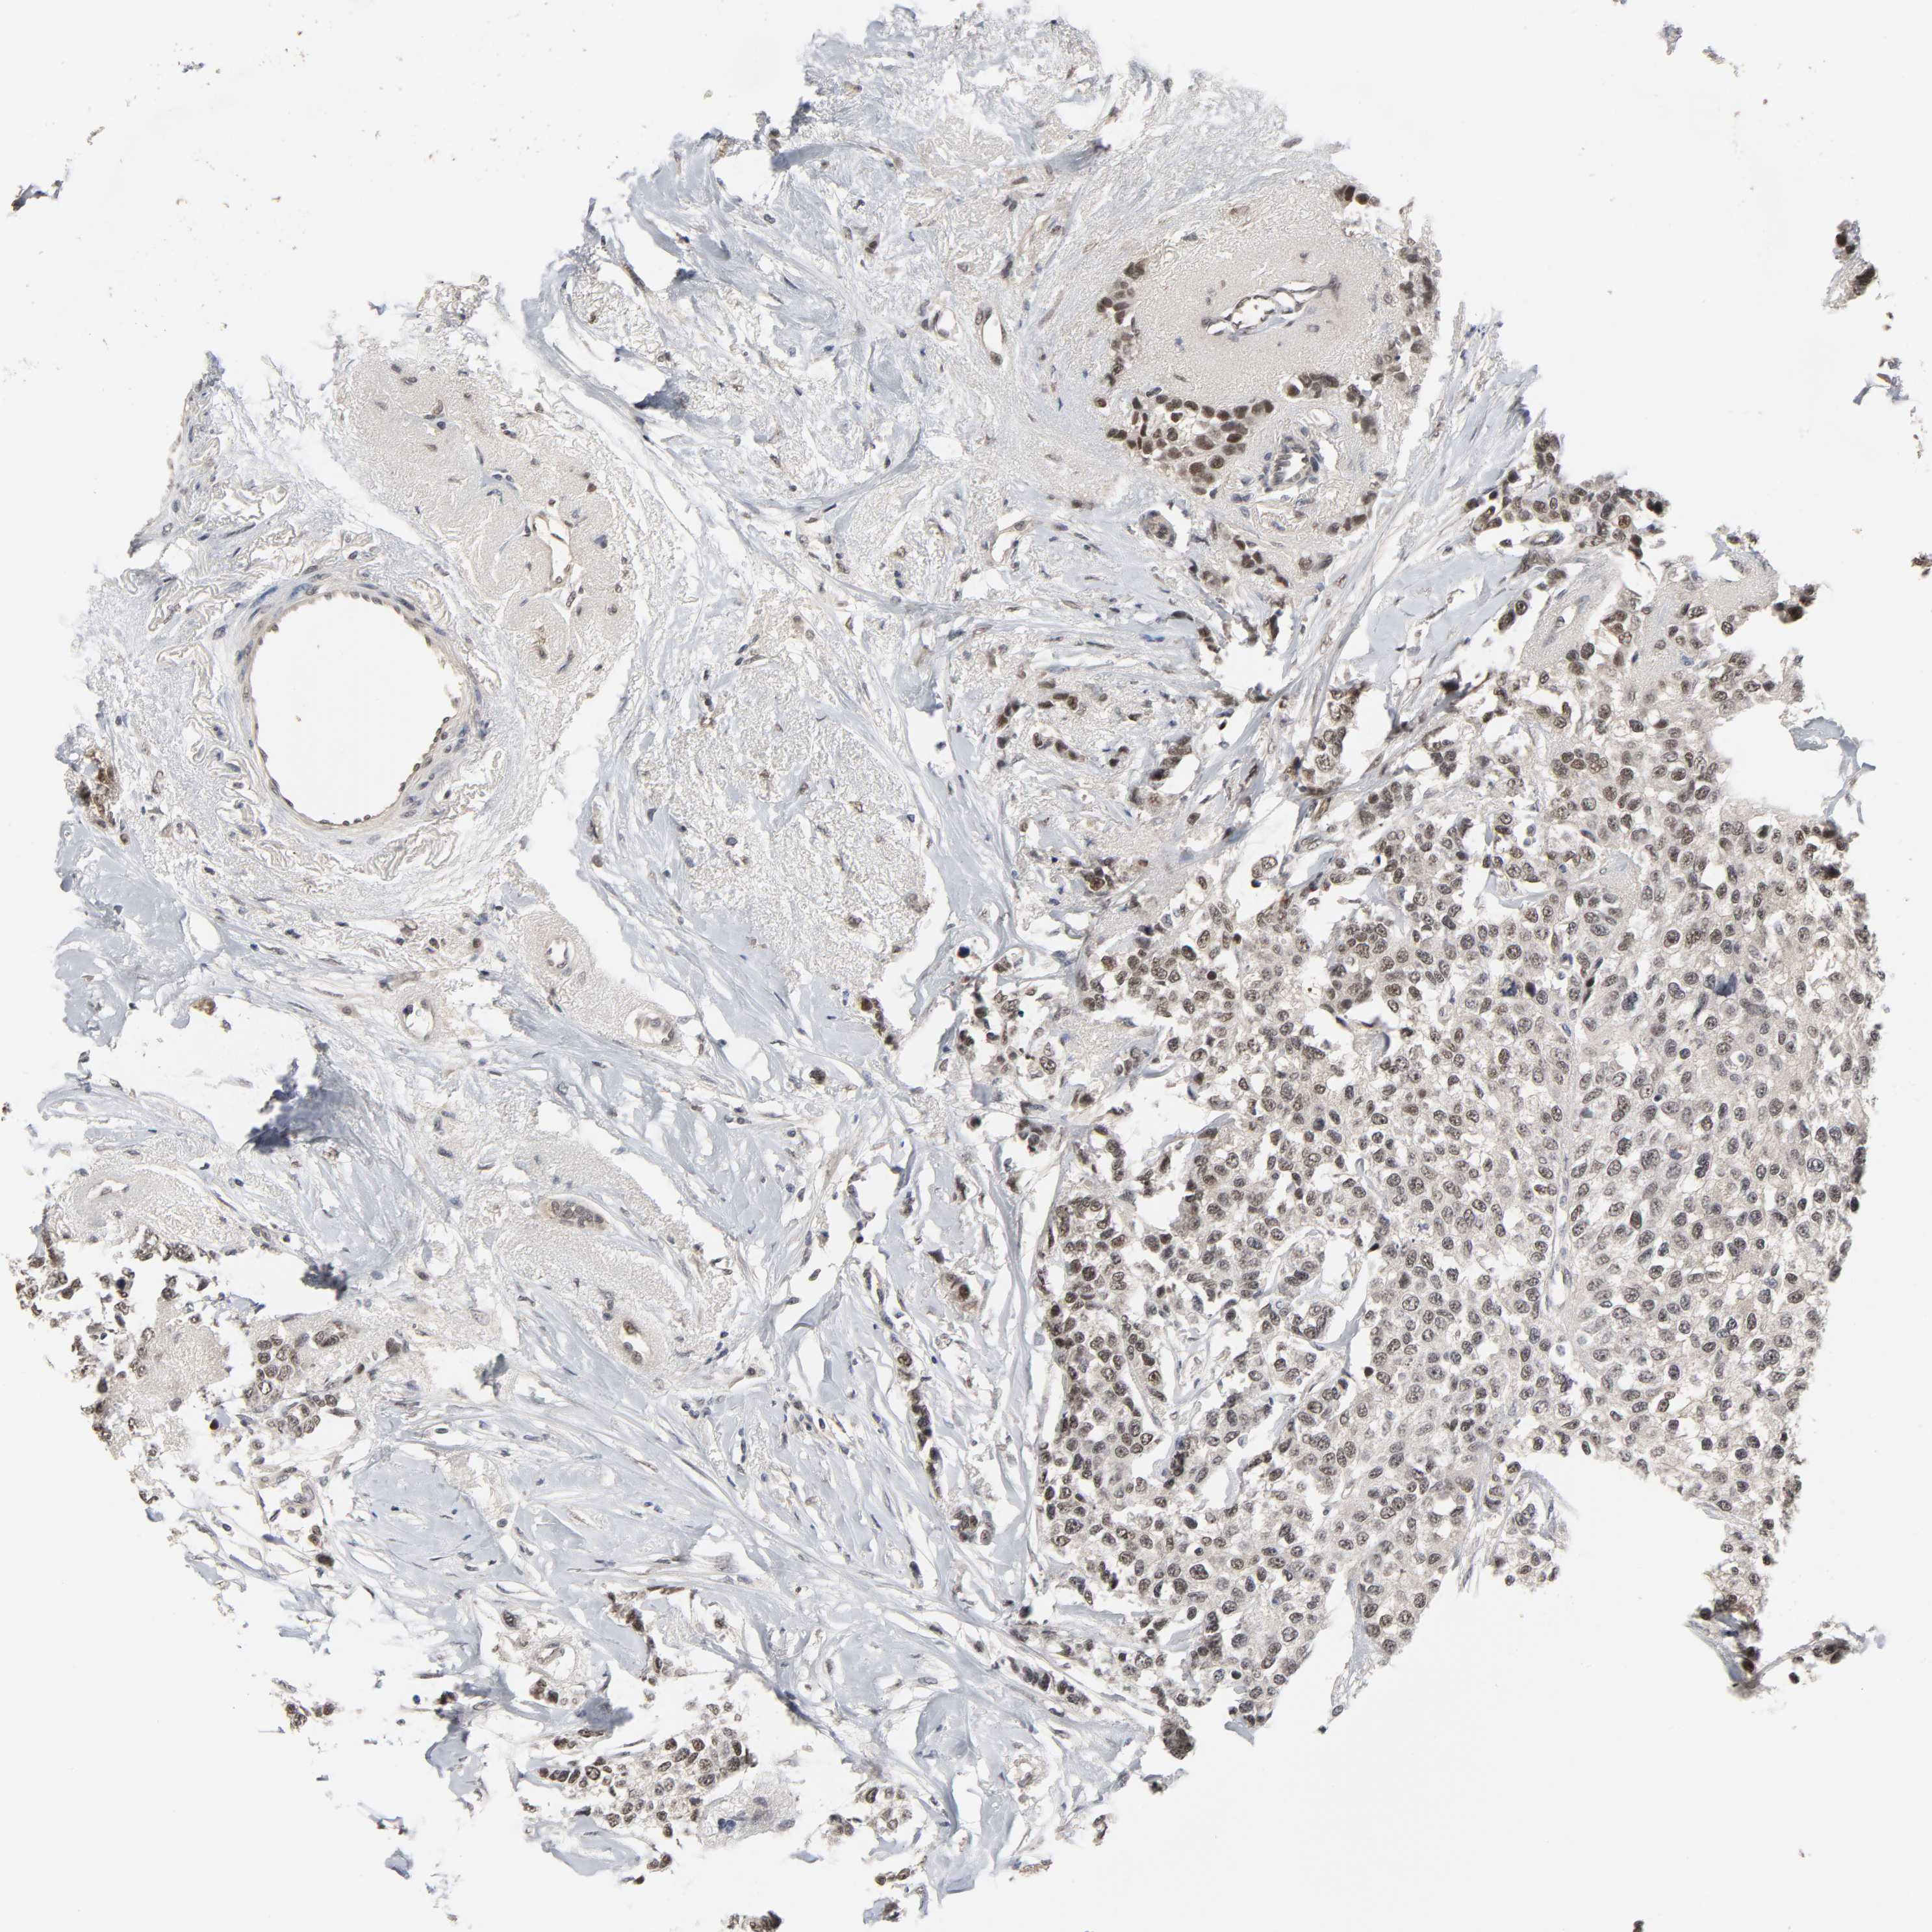

CANCER BREAST CANCER Show tissue menu

BRCA TCGA BRCA VALIDATION PROTEIN EXPRESSION